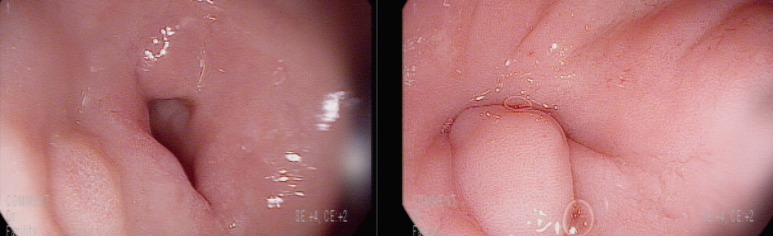

위각부 궤양

전반적인 만성 표재성 헬리코박터 위염 소견

십이지장의 구축으로 인한 협착 상태, 내시경 통과는 문제 없다.

위각부에 거의 아물어 있는 궤양 소견